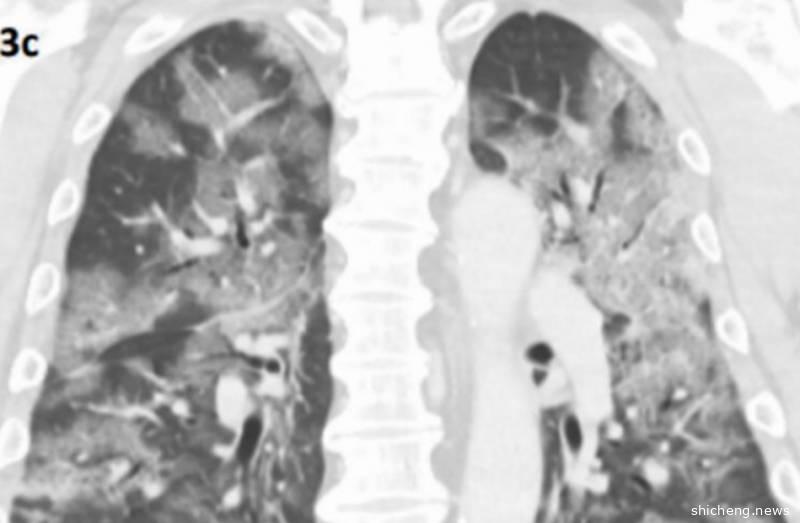

最近,新加坡首次公开扫描影像

新冠肺炎患者肺部出现“碎石路”阴影

图源:樟宜综合医院的研究团队